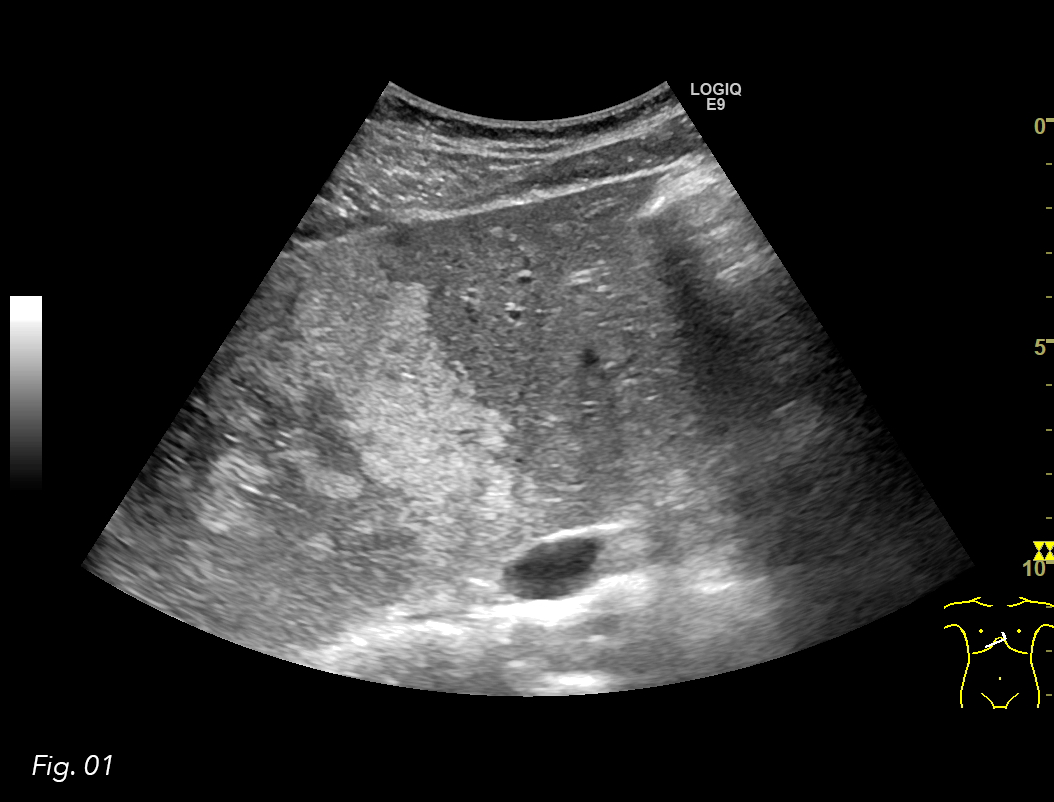

An ultrasound examination of the abdomen was performed using a GE Logiq E9 system with a curved array transducer and a frequency of 1-6 MHz. The patient was examined in the supine position. The examination revealed a large hyperechoic area in the liver hilum surrounding the portal vessels, involving segments IV, V and VIII. The lesion had an irregular borders, but the remaining liver parenchyma appeared normal (Fig. 1, 2).

Fig. 1: US image of the liver. Transverse plane of the segments II and IV, where the difference between normal liver and the parenchyma with focal fatty infiltration is seen.